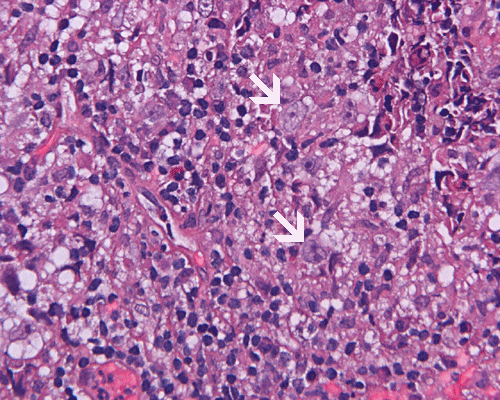

Paraffin sections: The entire volume of the tissue is made up of a granulomatous inflammation with poorly formed granuloma (Panel F, G, and H). The density of the lymphocytes is variable in different areas. In some areas, there is a rather intense lymphocytic infiltration accompanied by scant atypical cells with enlarged nulcei and prominent nucleoli (arrows in Panel I and J, Panel J is a higher magnification of Panel I). These atypical cells are quite easy to be missed. No microorganisms were identified by acid fast stain, PAS stain or GMS stain. The lymphocytes but not the atypical cells are positive for CD20 (Panel K) or CD3 (Panel L). The granulomatous background is strongly positive for CD68 (Panel M). Only rather faint positive staining for placental alkaline phosphatase (PLAP) is demonstrated and the interpretation is difficult as they are present in areas with crush artifact (Panel N). Many of the large, atypical cells are positive for CD117 (c-kit) (Panel O).

Intracranial germinoma is histologically identical to ovarian dysgerminoma and testicular seminoma. There is a tendency to infiltrate adjacent structures and to spread throughout the ependyma, the ventricular system and subarachnoid spaces. Microscopically, they consist of nests, lobules, cords, and/or sheets of large round tumor cells with well-defined borders, clear to pale cytoplasm with artifactual vacuolization, round and centrally located nuclei with open chromatin and prominent round or bar-shaped nucleoli. The cytoplasm is glycogen-rich, making these cells periodic acid-Schiff (PAS)–positive and diastase sensitive. These tumor cells are mitotically active. Atypical mitosis, however, is not a common finding. Necrosis is usually not prominent.  In the most classic histologic picture, clusters and cords of large germinoma cells are separated by a dense, lymphocytic infiltration admixed with some macrophages and a delicate fibrovascular network. Plasma cells may be found. At medium-power magnification with hematoxylin and eosin stain, the contrast between the smaller, darkly staining lymphocytes and the larger, pale staining cytoplasm of neoplastic cells is virtually pathognomonic. The amount of inflammatory cells can have wide variations among different tumors. In some occasions, the large germinoma cells are difficult to be found and the overall picture may suggest a lymphoma. Syncytiotrophoblastic cells can also be present. These cells should not be mistaken as evidence of choriocarcarcinoma.

Granulomatous changes are common findings in germinomas and intracranial germinomas follow this general trend 3, 4, 5. It can be extensive. This feature is particularly problematic in neuropathologic when stereotactic biopsy is performed and the amount of tissue available for examination is limited as illustrated in this case. During intraoperative consultations, a frozen section diagnosis of granulomatous inflammation should prompt additional sampling as isolated granulomatous inflammation of infectious origin and sarcodosis are quite uncommon in the pineal gland.